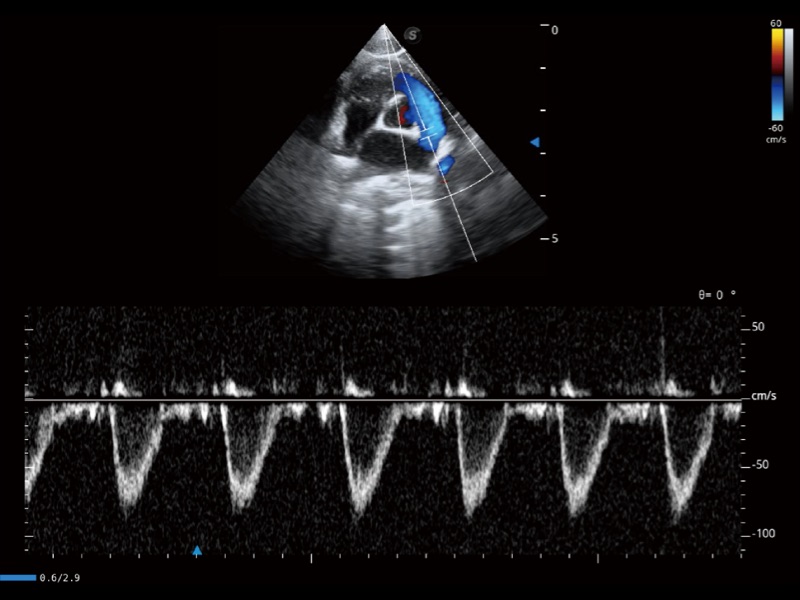

通過創(chuàng)新的 Matrix E自適應(yīng)濾波器和超長時間域算法,極大提升超低速微細血流的檢出能力,同時更精準地濾除軟組織和噪聲信號,為獸用醫(yī)生提供以往無法通過常規(guī)血流獲得的疾病診斷信息。

通過色彩血流和實時寬景相結(jié)合,可觀察到完整的靜脈或動脈的血流,方便醫(yī)生檢查。實時掃查過程中,如有任何操作失誤也可以很容易地進行回掃擦除,而不會中斷掃查。